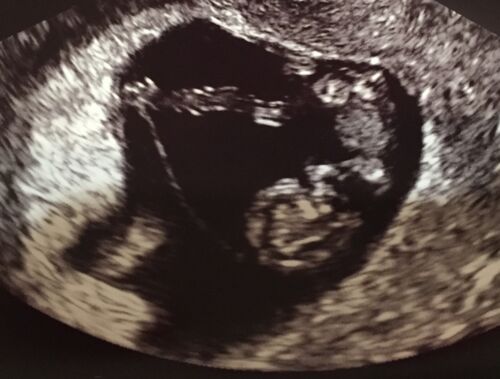

いよいよ2017年も終わりが近づきましたね!今年も大変お世話になりました。 普段ですとここで1年の仕事のことや個人の活動などをまとめてゆくところなのですが、今年は人生最大の変化とも言えるかもしれない、家族が増えるという体験をしました。これをきち…